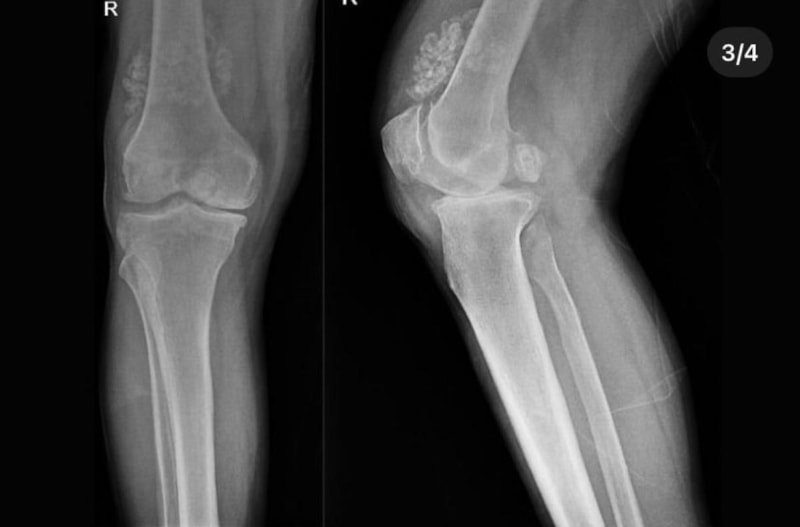

Doktorlar, Düzce Üniversitesi Tıp Fakültesi Hastanesi'nde tedavi gören hastanın diz eklemi çevresinde "multipl sinovial kondromatozi" gördü.

Bunun üzerine ameliyata alınan hastanın dizinden 41 adet eklem faresi de denilen kemik parçası çıkarıldı.

Özellikle diz eklemi çevresinde görülmekle birlikte kalça, dirsek ve diğer eklemlerde de görülen, ufak parçalardan oluşan cisimler olarak tanımlanan eklem faresi, eklem çevresinde eklem sıvısı ya da sinoviyumda görülen kıkırdak ya da kemik parçalarıdır.

Eklem farelerinin boyutları birkaç milimetreden birkaç santimetreye kadar çıkabiliyor.